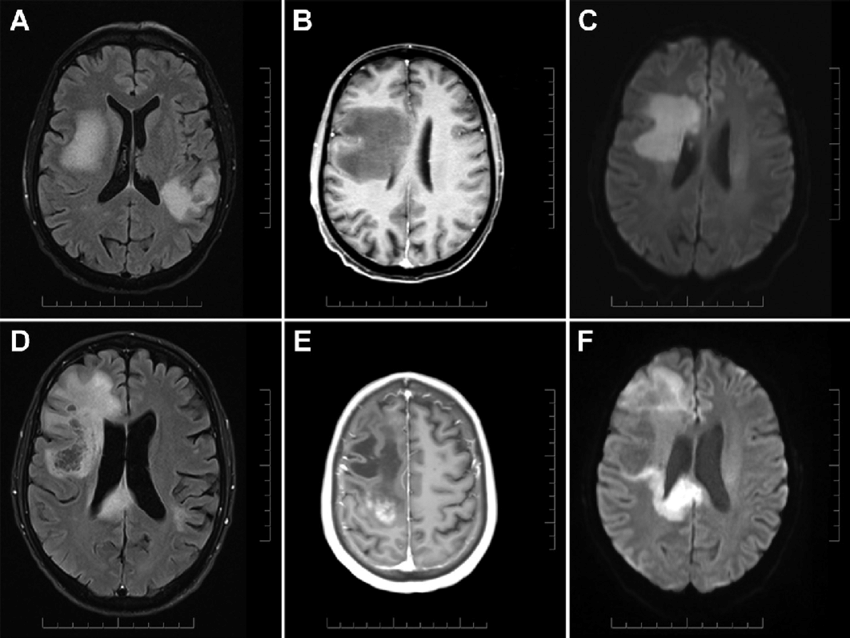

Our app allows a user (preferably a doctor) to enter in an MRI scan of the brain. With this MRI scan, our deep learning model takes in this image, and outputs a prediction. This prediction could tell a doctor if the patient has no tumor, or if they may have a pituitary or glioma/meningioma tumor.

We had built the model using TensorFlow with the Keras API, and 5,000 training images of MRI scans. With TensorFlow, we are able to create state of the art models or applications in a fraction of the time. We used OpenCV and NumPy to preprocess the images. For example, greyscaling and resizing images are a key part of preprocessing and getting the image data in the right format. For the web app, we used HTML and bootstrap CSS, with a turquoise UI, to make the web app even more clean.